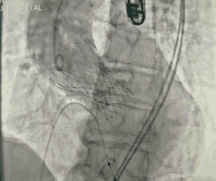

今天直播的这位患者是85岁的老年男性,10年前因主动脉瓣重度狭窄植入CoreValve 26mm瓣膜,是我国第一例TAVR患者,术后恢复情况良好。

6个月之前,患者出现反复胸闷气急,心超提示人工生物主动脉瓣置换术后,中重度主动脉瓣口反流,轻度瓣周漏。这例患者目前已85岁,同时合并持续性房颤、高血压、心功能不全Ⅲ级,STS评分7.56%,外科手术风险高危。

葛均波院士、周达新教授结构团队对这位生物瓣衰败的老年男性患者行瓣中瓣植入术,术中选择了23mm VenusA-Valve(杭州启明),植入过程顺利,术后冠脉无堵塞,未出现瓣周漏,术后跨瓣压差接近于0,赢得了参会专家的激烈掌声。

图3 TAVR瓣膜释放前造影

图4 TAVR球囊前扩张

图5 TAVR瓣膜释放后